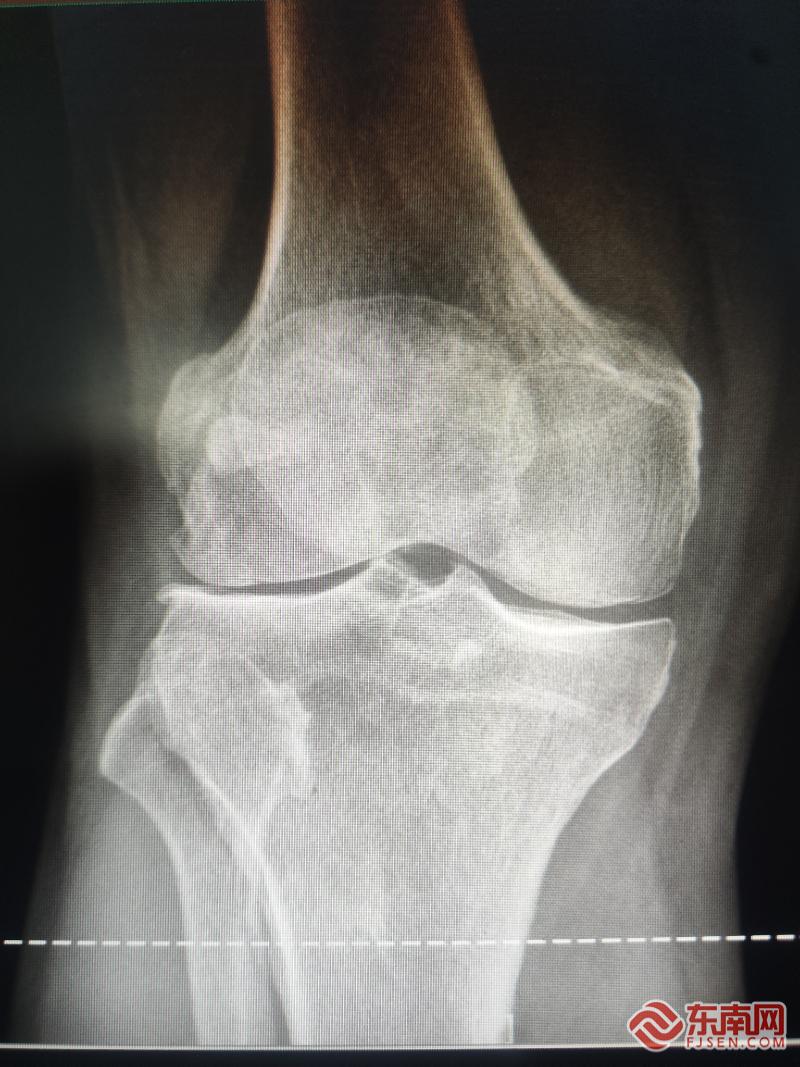

术前片。宁德市中医院供图

据悉,此次手术由孙永强名医工作室核心成员、河南省洛阳正骨医院郑州院区膝关节外三科申晟副主任医师主刀完成。患者常年饱受膝关节骨关节炎困扰,影像学检查显示其病变主要局限于膝关节外侧间室,经孙永强教授团队联合会诊、精细评估与方案规划后,决定采用创伤更小、恢复更快的膝关节外侧单髁置换术,精准破解患者病痛。